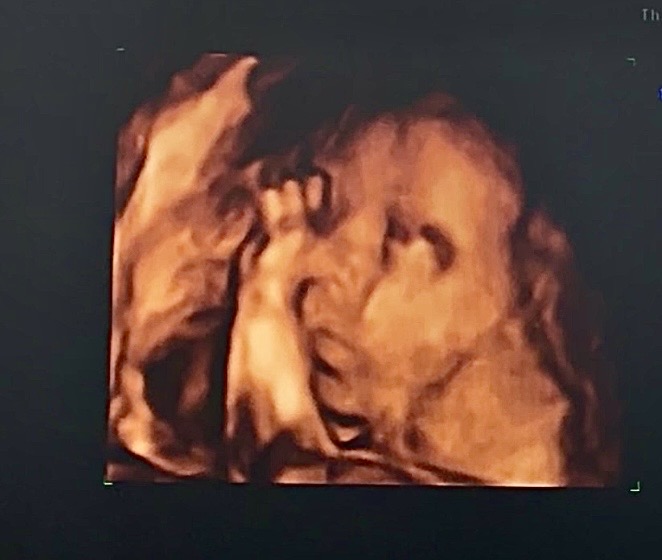

Maleńka już coraz większa - 705g, dalej mniejsza niż być powinna, ale w normie.

A tutaj fotka:

https://zapodaj.net/plik-UMlCl7Leqd

👧🏼 nr 1 - 2020

👶🏼 nr 2 - in progress

it's a girl! 🩷

09.12 - I prenatalne - 160g ✅

03.02 - II prenatalne - 350g ✅

02.03 - 705g ✅

30.03 - ⏳